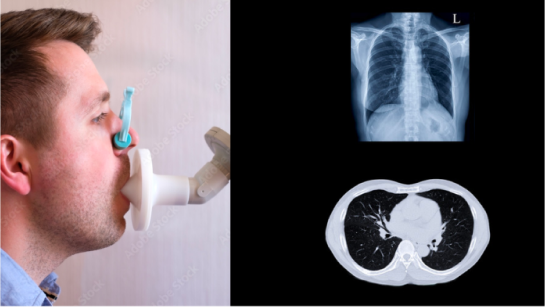

Perform Spirometry + DLCO + Chest

X-ray. Depending on the results, a high-resolution chest CT will be considered

Respiratory function tests can aid in diagnosis and can provide information on extent and severity of the disease. For more related information

For RA-ILD risk score of 5 or 6, perform spirometry + DLCO + chest X-ray. Depending on the results, a high-resolution chest CT will be considered